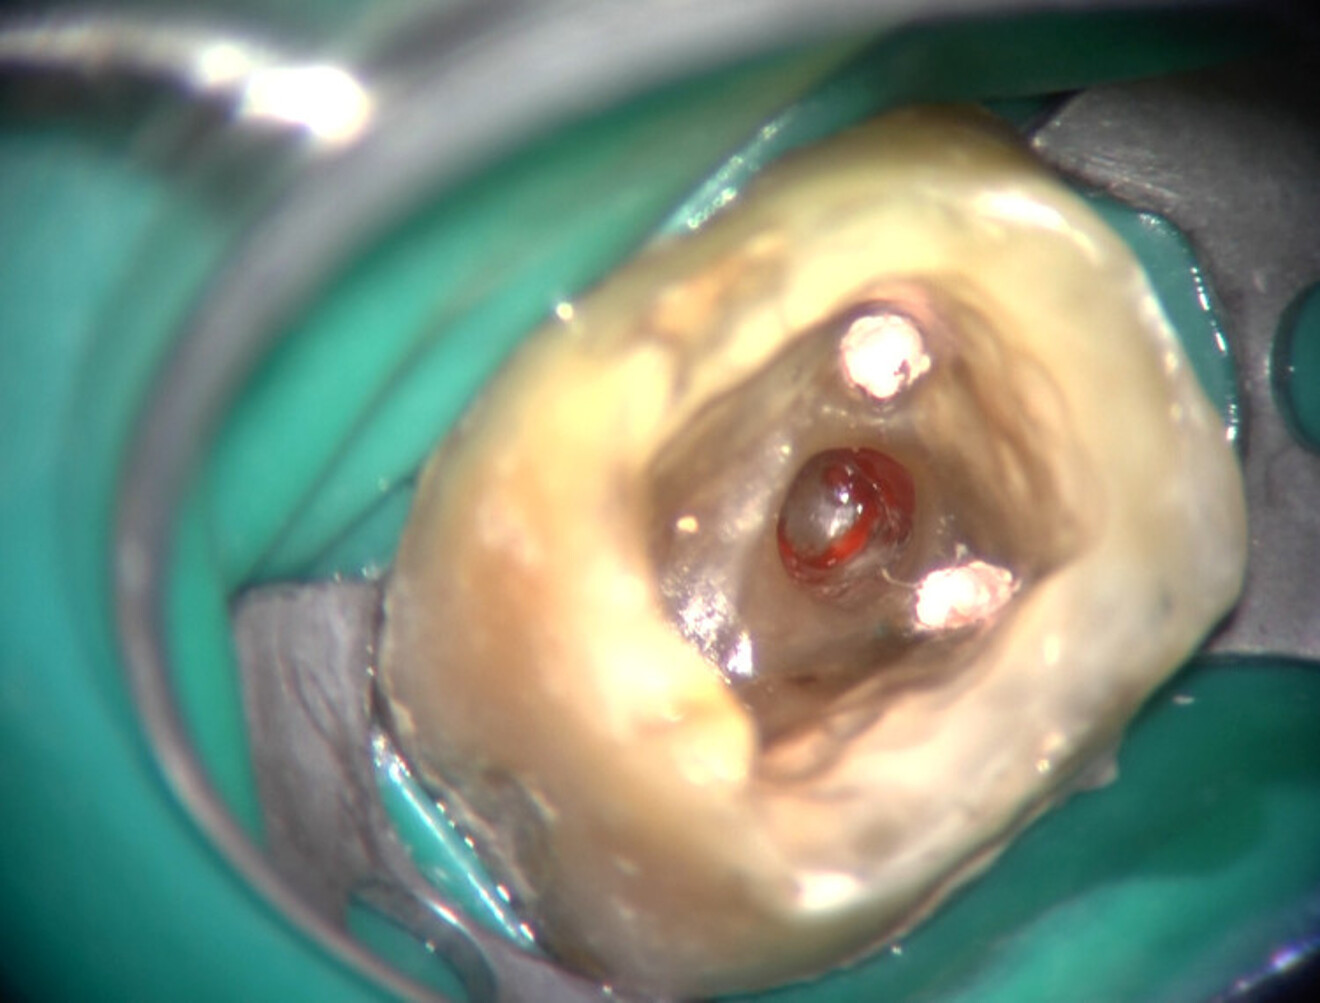

D’un point de vue pratique, la première étape consiste à réduire les dimensions du tenon s’il occupe une grande partie de la structure coronaire, de préférence en lui donnant une forme cylindrique similaire à celle d’un tenon préfabriqué. De même, une reconstitution corono-radiculaire coulée ancrée dans plusieurs canaux doit d’abord être sectionnée jusqu’au niveau du plancher de la cavité pulpaire, afin de la traiter comme un ensemble de tenons unitaires, ce qui diminue le degré de rétention global du système. La réduction du tenon doit être effectuée avec des fraises en carbure spécialement conçues pour découper le métal, sous une irrigation abondante. Les évaluations cliniques et radiographies préliminaires sont essentielles pour planifier l’angle de coupe. La procédure doit être fréquemment vérifiée et, si nécessaire, il convient d’effectuer des contrôles radiographiques avant qu’une quantité excessive de dentine ne soit sacrifiée (Figs. 1–3).